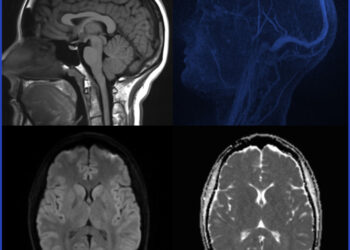

Skaityti daugiauDetailsVaikų insultas – tai sunki neurologinė būklė, kuri pasireiškia dar iki 18 metų amžiaus. Nors insultai dažniausiai siejami su vyresniais...